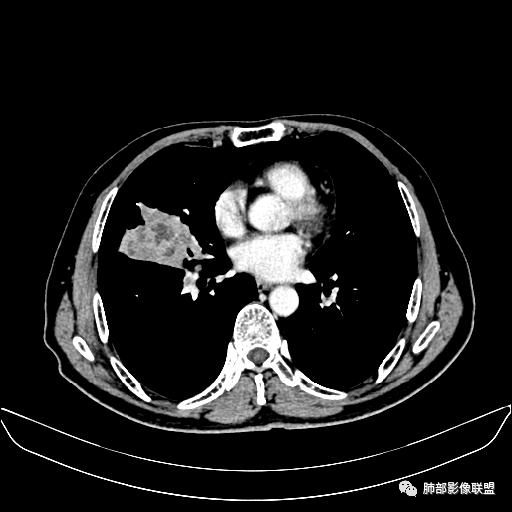

入院CT

老年男性,因“咳嗽咳痰1月余。”入院。病程中咳嗽咳痰,咳黄白痰,间断咯少许鲜红色痰血。PPD阳性。胸CT:右肺中叶外侧段支气管管腔阻塞,大片实性病变,病灶边缘光滑,部分边缘膨隆,可见分叶,肺门及纵隔可见肿大淋巴结,并可见钙化。增强可见病灶明显强化,而且延迟强化明显,病灶内多发低密度区,内见血管影,血管变细、部分血管破坏。考虑恶性病变可能性大,鉴别慢性肉芽肿性病变。

右肺中叶外侧段管腔阻塞、实性病变,病灶边缘光滑,可见分叶,肺门及纵隔可见肿大淋巴结,并可见钙化。增强可见病灶内多发低密度区。

老年男性,咳嗽、咳痰1月余,间断血痰。PPD阳性。

胸CT:跨叶大肿块,主体在中叶,右中叶外侧段支气管阻塞,病灶部分边缘膨隆,可见分叶,部分边缘平直,肺门及纵隔可见肿大淋巴结。增强病灶不均匀强化,延迟强化明显,病灶内多发低密度区,内见血管飘浮,部分血管变细、模糊。考虑:恶性病变可能性大,大细胞?淋巴瘤?鉴别慢性肉芽肿性病变。

右肺中叶软组织肿块,外围向内生长,叶间胸膜向前内移位,肿块近肺门侧跨叶,中叶外侧段支气管截断,密度不均匀,双侧肺门及隆突下见肿大淋巴结,增强后呈中度不均质强化,肺动脉供血,多发坏死区,边界尚清,坏死区域内见结构,结合病史考虑恶性,鉴别诊断1结核,爬行征是沿支气管树分布,外宽,内窄,周围有卫星灶,内气管狭窄后扩张,此例沿叶间胸膜长轴分布,气管有截断,不典型。2炎性肉芽肿,符合的地方下方层面增强后延迟性轻度环形强化,不符临床无发热等急性感染病史,实验室指标不符,病灶周围渗出及慢性炎性改变有,不明显。